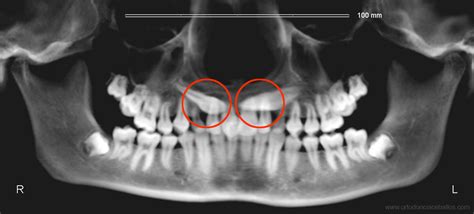

Un canino incluido es un término utilizado en odontología para describir un diente que, por diversas razones, no ha logrado erupcionar correctamente en la cavidad oral y, en su lugar, se encuentra atrapado o retenido en el hueso maxilar o mandibular, o en el tejido blando circundante. La inclusión de caninos es más común en la arcada superior, aunque también puede afectar a los caninos inferiores.

Estos dientes se encuentran atrapados dentro del hueso maxilar o en tejido blando, lo cual puede generar diversos problemas, como maloclusiones, daños a dientes vecinos, infecciones o incluso quistes. Cuando se diagnostica un canino incluido, es fundamental que el paciente reciba una atención odontológica adecuada y oportuna para prevenir o minimizar los problemas asociados a esta condición.

Consiste en una pequeña intervención quirúrgica en la que se realiza una ventana en el hueso (fenestración) a través de la cual se expone la corona del canino incluido, para poder colocar después un dispositivo de tracción ortodóncica que tire del diente para llevarlo a su sitio. Este tratamiento debe ser coordinado entre el cirujano y el ortodoncista, que previamente habrá ido creando el espacio necesario para el diente en la arcada.